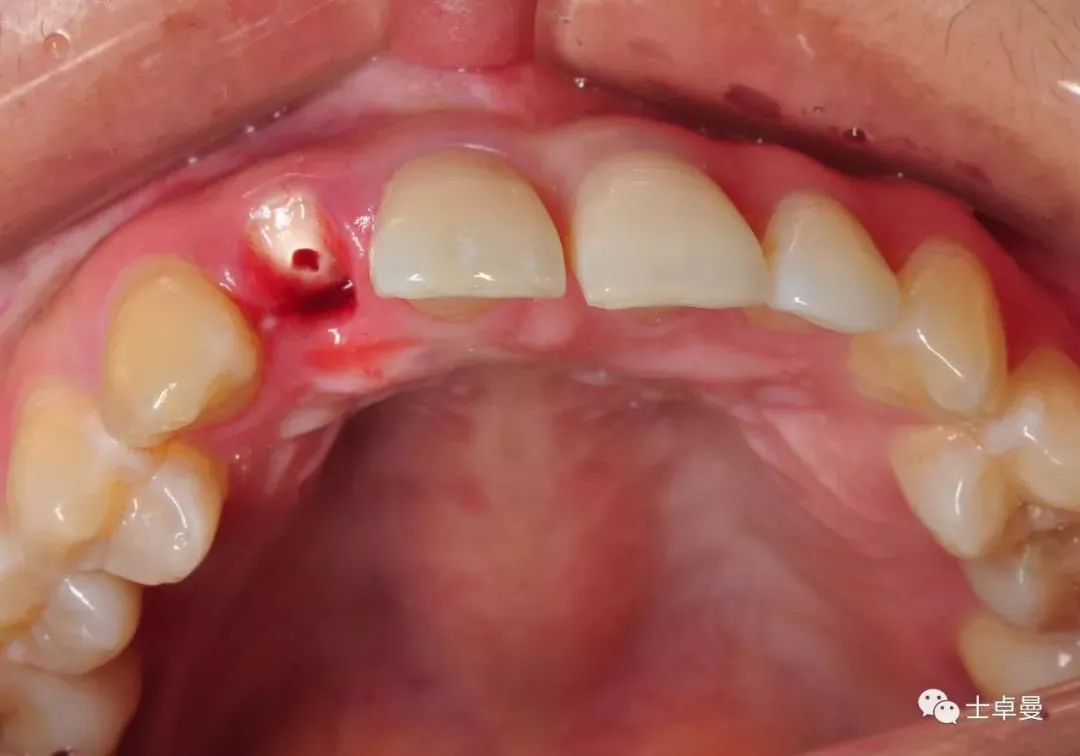

术前口内照

断根舌侧劈裂至龈下3mm-4mm

·        唇侧龈缘曲线完好,与邻牙协调,牙龈质地健康,无炎症,薄龈型;

·        残根不松,叩诊不适;

·        11、21之间有约1mm-1.5mm缝隙;